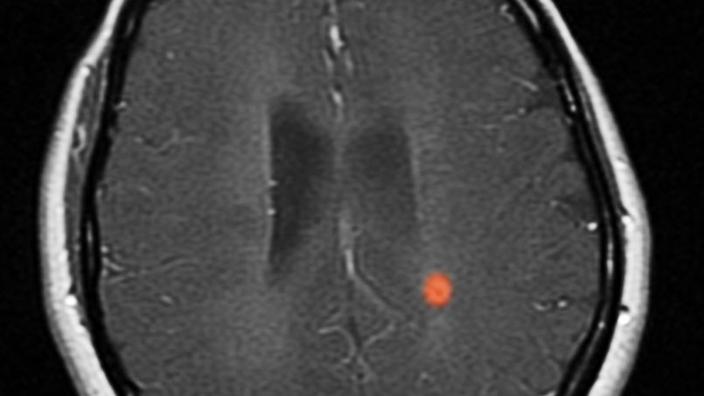

L irm est un examen diagnostique très intéressant en cas de sclérose en plaques car il permet de visualiser les plaques de démyélinisation avec une grande.

L irm encéphalique et médullaire est l examen de choix pour le diagnostic de sclérose en plaques les lésions apparaissent sous la forme d hypersignaux de la substance blanche sur les séquences pondérées en t2 le lcs apparaît blanc lors de ces séquences ou en flair fluid attenuation inversion recovery qui est une séquence t2 avec inversion de la couleur du lcs. Les irm sont réalisées par un neuro radiologue de préférence dans le même centre ou service de radiologie et les résultats seront interprétés par votre neurologue qui connaît bien l histoire de votre maladie.